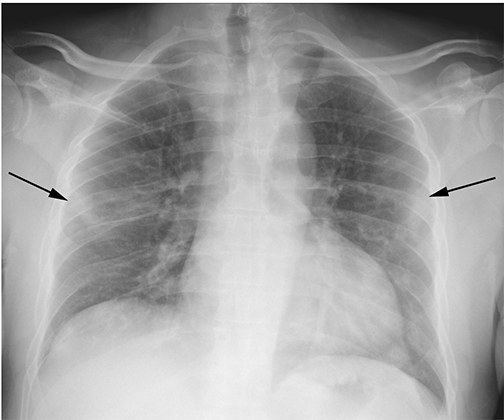

The radiologists conducted a retrospective study of nearly 400 persons under investigation (PUI) for COVID-19 in New Orleans. They reviewed the patients’ chest x-rays along with concurrent reverse-transcription polymerase chain reaction (RT-PCR) virus tests. Using well-documented COVID-19 imaging patterns, two experienced radiologists categorized each chest x-ray as characteristic, nonspecific, or negative in appearance for COVID-19.“The presence of patchy and/or confluent, band-like ground glass opacity or consolidation in a peripheral and mid-to-lower lung zone distribution on a chest radiograph is highly suggestive of SARS-CoV-2 infection and should be used in conjunction with clinical judgment to make a diagnosis,” says Bradley Spieler MD, Associate Professor of Diagnostic Radiology and Vice Chairman of Research in the Department of Radiology at LSU Health New Orleans School of Medicine.